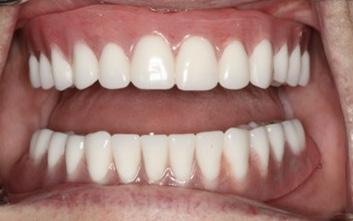

After three months of healing, the patient returned to the AEGD clinic to confirm osseointegration of implants and to begin the overdenture fabrication process. At the final impression appointment, signs of arthritis including knuckle enlargement were noted. Due to this finding, it was determined that changing the patient's final prosthesis from a Conus overdenture to a conventional overdenture was in the best interest of the patient, as the Conus would be too cumbersome for her. As seen in Figures 1 and 2, the outcome turned out very well and the patient was pleased with results and esthetics.

FIGURE 1

FIGURE 2